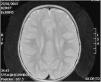

La resonancia magnética cerebral a los 2 años mostró alteración en la mielinización (fig. 2). Actualmente, a los 6 años, presenta discapacidad intelectual leve e hipotonía axial con espasticidad de miembros inferiores, que imposibilita el desplazamiento autónomo.

Los casos 2 y 3 son hermanas en una familia sin consanguinidad referida. Al nacimiento a las 34 y 36 semanas de gestación, respectivamente, ambas presentaron ictiosis moderada, descrita como lamelar. Fueron capaces de mantener sedestación sobre los 9 meses y deambulación autónoma entre los 4 y 6 años. La paciente 2 aún mantiene deambulación autónoma a los 22 años. Ambas desarrollaron signos de espasticidad durante los 2 primeros años de edad, y tras la obtención de neuroimagen con alteración de la mielinización, se sospechó el diagnóstico.